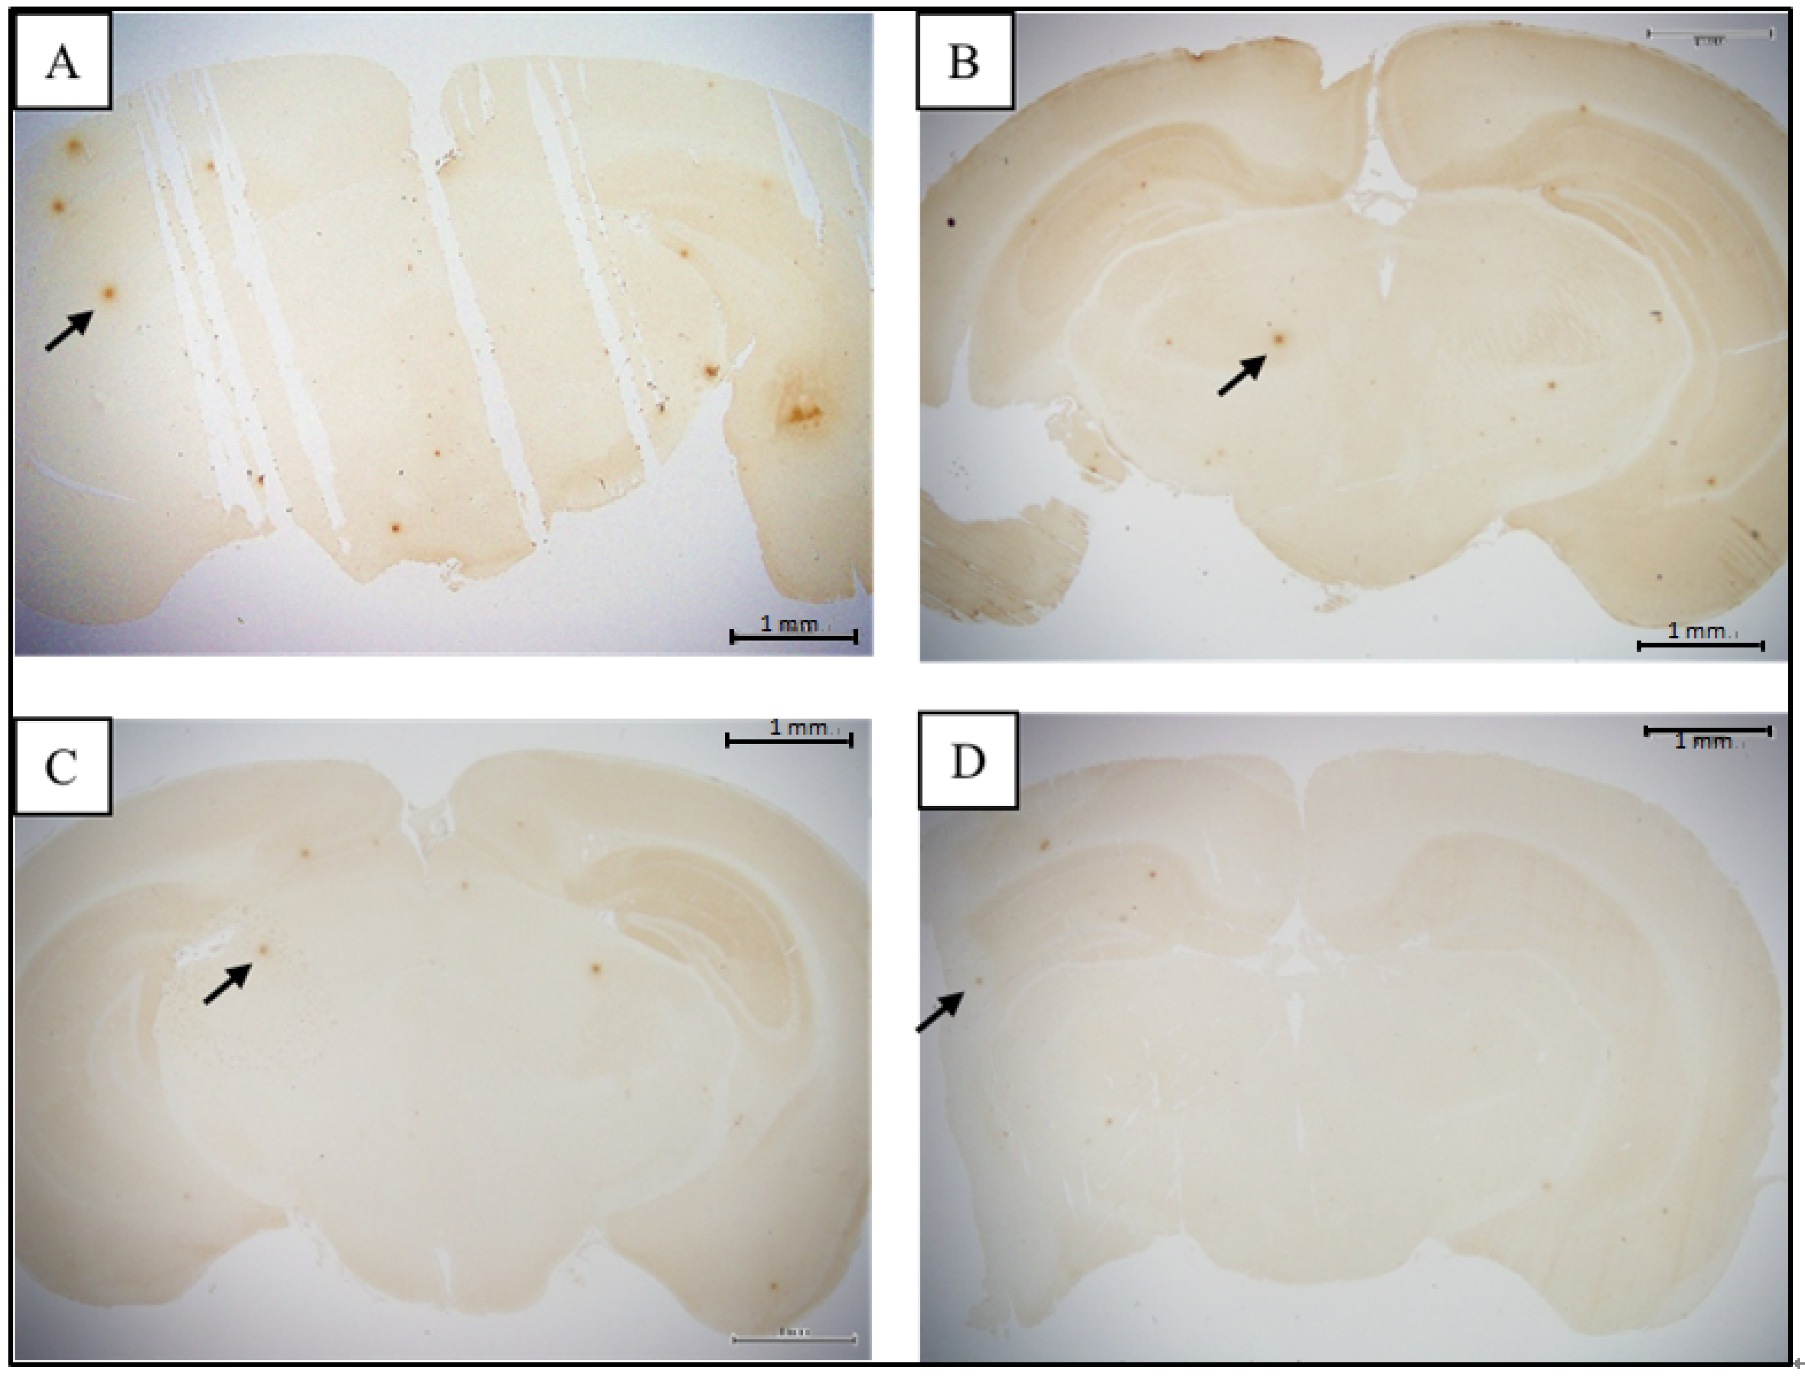

3.2. Comparison of Brain Pathological Markers